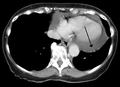

A CT scan image showing a pericardial effusion

A CT scan image showing a pericardial effusion A very large hemorrhagic pericardial effusion due to malignancy as seen on ultrasound. closed arrow: the heart, open arrow: the effusion